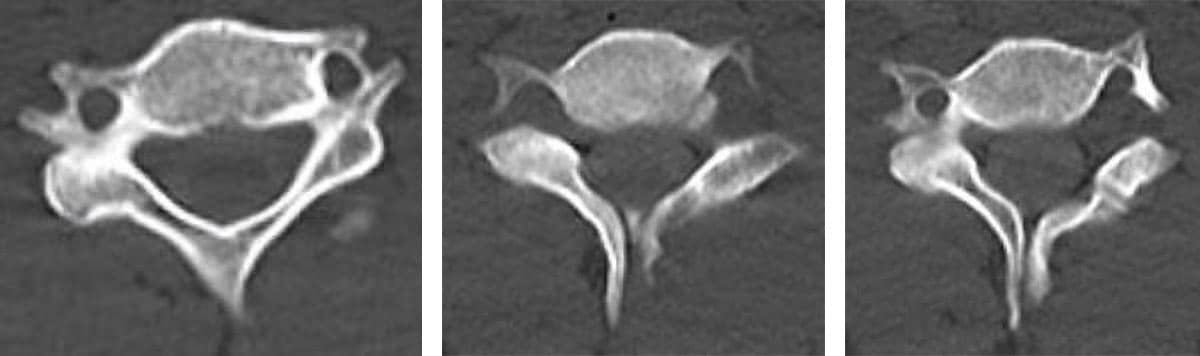

「4、5日前から、ふわふわして体の重心が定まらない感じ、バランスボールに乗っているような感じがするので来てみました」と22歳の男性が来院した。神経学的検査は正常で、頚部の後屈時にややカクカクとひっかかる感じがする以外、前庭・小脳系、後索症状も含めて主訴を裏付ける他覚的徴候を認めなかった。頸椎の異常があるかもしれない、という思いから、原因検索のために頚髄MRIを撮ったところ、脊髄空洞症が見つかった。1週間後に来院した際には、「昨日の朝から左の親指あたりがしびれてきました。身体が前と右にひっぱられる感覚が出てきています」という訴えがあったために、空洞の拡大が進行して脊髄の圧迫障害が強くなっている可能性を考えて、地域の基幹病院脳外科にreferした。

教科書的には「中吊り型知覚障害」「解離性感覚障害」「筋委縮」などが有名だが、病状が進み、神経障害が悪化してからの症状であるから、診断が治療に結び付かないことも多いだろうと思う。

結局、お願いした病院で精査してくれた結果、頸椎には二分脊椎を含めた奇形があり、これによる末梢神経障害が、脊髄空洞症の症状悪化と捉えられた可能性も分かった。以下にその画像を載せておく。